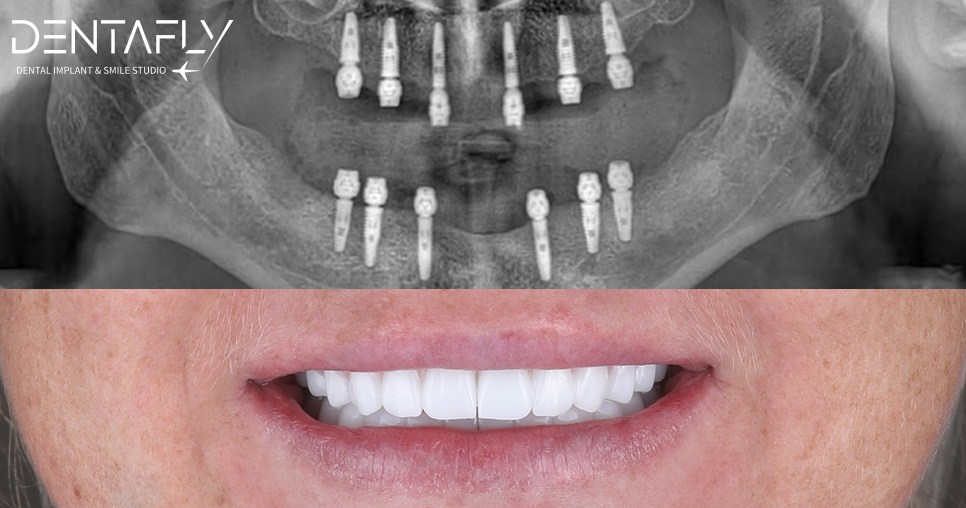

Witness the Transformation: All on 6 Before & After

A permanent full-arch restoration is a masterclass in surgical precision and prosthetic design. Explore our gallery to see how the All on 6 protocol translates into real-world transformations for UK patients—natural finish, restored facial volume, and harmonious smiles.

Witness Digital Precision: The Smile Design Gallery

A flawlessly engineered smile is a masterclass in digital predictability. Explore our exclusive visual gallery to see how advanced 3D planning translates into breathtaking real world transformations for our actual UK patients.